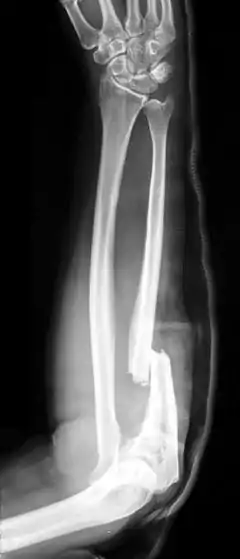

| Isolated fracture of the ulna (known as a nightstick fracture) | |

An ulna fracture is a break in the ulna bone, one of the two bones of the forearm.[3] If the fracture occurs as a single break in the middle of the ulna it is known as a nightstick fracture.[2] It; however, is often associated with a dislocation or fracture of the radius, the other forearm bone.[4][5] Complications may include nonunion.[1]

Fractures of the ulna can occur at different levels of the bone: near the wrist, in the middle or near the elbow.[3] The fracture may be confined to the ulna or accompanied with damage to the radius or the wrist or elbow joints.[3]

- Nightstick fracture is a fracture of the middle portion of the ulna without other fractures, and with both wrist and elbow joints preserved.[7]